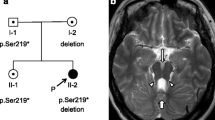

A two-year-old boy was born to a nonconsanguineous couple by cesarean section with a birth weight of 3.42 kg, and the boy’s global development was delayed. He raised his head at 4 months, turned over at 8 months, sat all by himself at 10 months, crawled at 24 months, and stood with support at 28 months. The boy spoke with only monosyllables but had no other verbal communication skills. He had moderate intellectual disability evaluated by the Chinese Developmental Scale for children aged 0–6 years (WS/T 580–2017). The boy had a height of 95 cm (+ 2 SD), weight of 12.4 kg (0 SD), and occipitofrontal circumference of 53 cm (+ 3 SD) at 2 years. Physical examination showed frontal prominence, right eye esotropia, hypotonia and lower myodynamia. Ultrasonic examination showed normal liver, gallbladder, spleen, kidneys, ureter and bladder. Magnetic resonance imaging of his brain revealed unclear vermis of cerebellum, superior cerebellar peduncle thickening and lengthening (a clear molar tooth sign) as well as cerebellar hemispheres joining in the midline of brain and a smaller midbrain (Fig. 1). Thus, the boy was diagnosed with Joubert syndrome.

Brain magnetic resonance imaging (MRI) findings for the Joubert syndrome individual. Molar tooth sign with moderate cerebellar vermis hyoplasia, lengthening and thickening of superior cerebellar peduncles as well as superior cerebellar dysplasia as indicated by white arrows. a T2-weighted image. b T1-weighted image. c Pedigree of Joubert syndrome patient